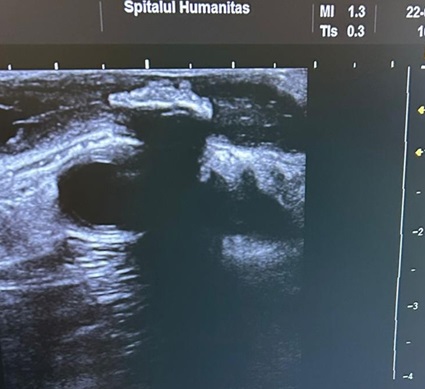

ECOGRAFIE

ecografie mamară

ecografie tiroidiană

puncție biopsie sân și ganglioni Tru-cat - pentru diagnosticul tumorilor maligne

puncție tiroidiană cu ac fin (FNAB) - pentru diagnosticul citologic al nodulilor tiroidieni

ecografii înainte și după chirurgia plastică (sân, perete abdominal, față)

Avantajele ecografiei intraoperatorii